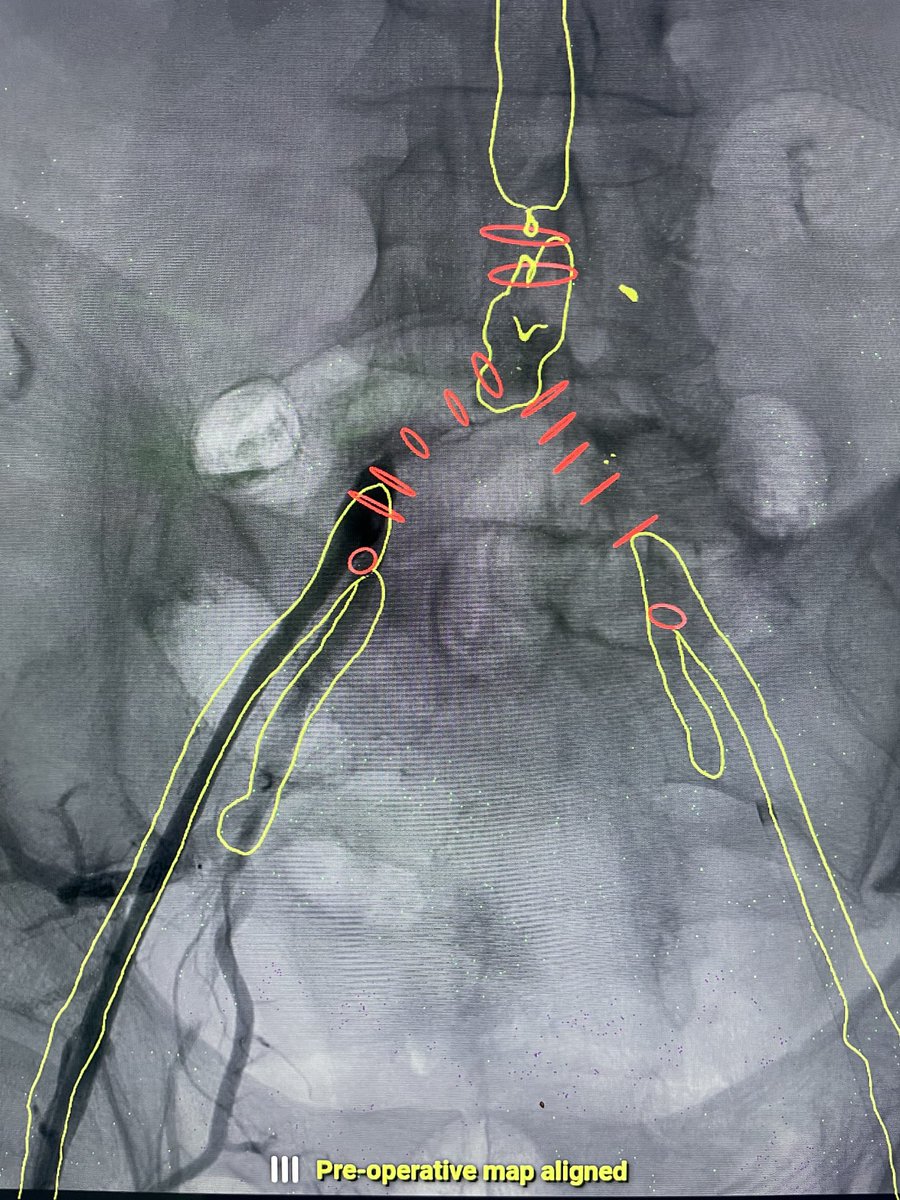

Listening to "Het aneurysma van de aorta abdominalis (AAA) met Patrick Vriens en Jan Heyligers" at methetmesaantafel.buzzsprout.com/1019002/120991…